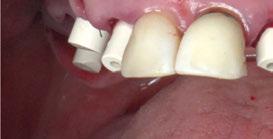

Figura 1a. Foto intraoral frontal inicial.

Figura 1b. Foto intraoral lateral izquierda inicial.

Figura 1c. Foto intraoral lateral derecha inicial.